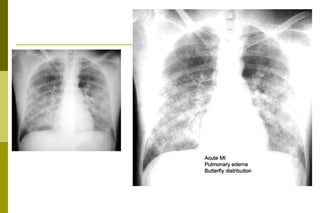

Edema pulmonar Definição: presença de líquidos no interior dos alvéolos pulmonares. O edema pulmonar ocorre em decorrência do desequilíbrio de fluidos através da barreira alvéolo-capilar. Patogenicamente pode ser classificado em: cardiogênico ou hidrostático,  por aumento da permeabilidade da barreira alvéolo-capilar, diminuição da pressão intersticial dos pulmões e  neurogênico.

Edema pulmonar Macroscopia Pulmões aumentados de peso, de cor avermelhada, firmes e deixando fluir quantidade variável de líquido.

Edema pulmonar Definição:presença de líquidos no interior dos alvéolos pulmonares. O edema pulmonar ocorre em decorrência do desequilíbrio de fluidos através da barreira alvéolo-capilar. Patogenicamente pode ser classificado em: cardiogênico ou hidrostático, por aumento da permeabilidade da barreira alvéolo-capilar, diminuição da pressão intersticial dos pulmões e neurogênico.

Edema pulmonar MacroscopiaPulmões aumentados de peso, de cor avermelhada, firmes e deixando fluir quantidade variável de líquido.

Caso clínico : EAP 68 anos, sabidamente hipertenso, com várias internações devido a crise hipertensiva. Iniciou com dispnéia subita e intensa, com eliminação de secreção “rósea”. Foi atendido no Pronto Socorro. PA: 200\120 mmHg. Ausculta pulmonar: diminuição do múrmurio e crepitações difusas. Apesar das medidas terapêuticas instituídas evolui para o óbito. Faça a correlação anátomo-clínica